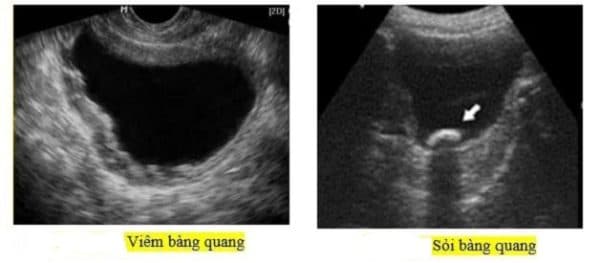

– Siêu âm: Xác định hình ảnh sỏi bằng sóng âm

Siêu âm phát hiện sỏi trong bàng quang

2.1 Viêm bàng quang – biến chứng sỏi bàng quang thường gặp

Việc sỏi liên tục cọ xát vào niêm mạc bàng quang gây ra chảy máu và nhiễm trùng, bàng quang bị tổn thương. Điều này dẫn đến người bệnh bị viêm nhiễm, bàng quang có mủ. Tình trạng này kéo dài dẫn tới viêm bàng quang mạn tính.